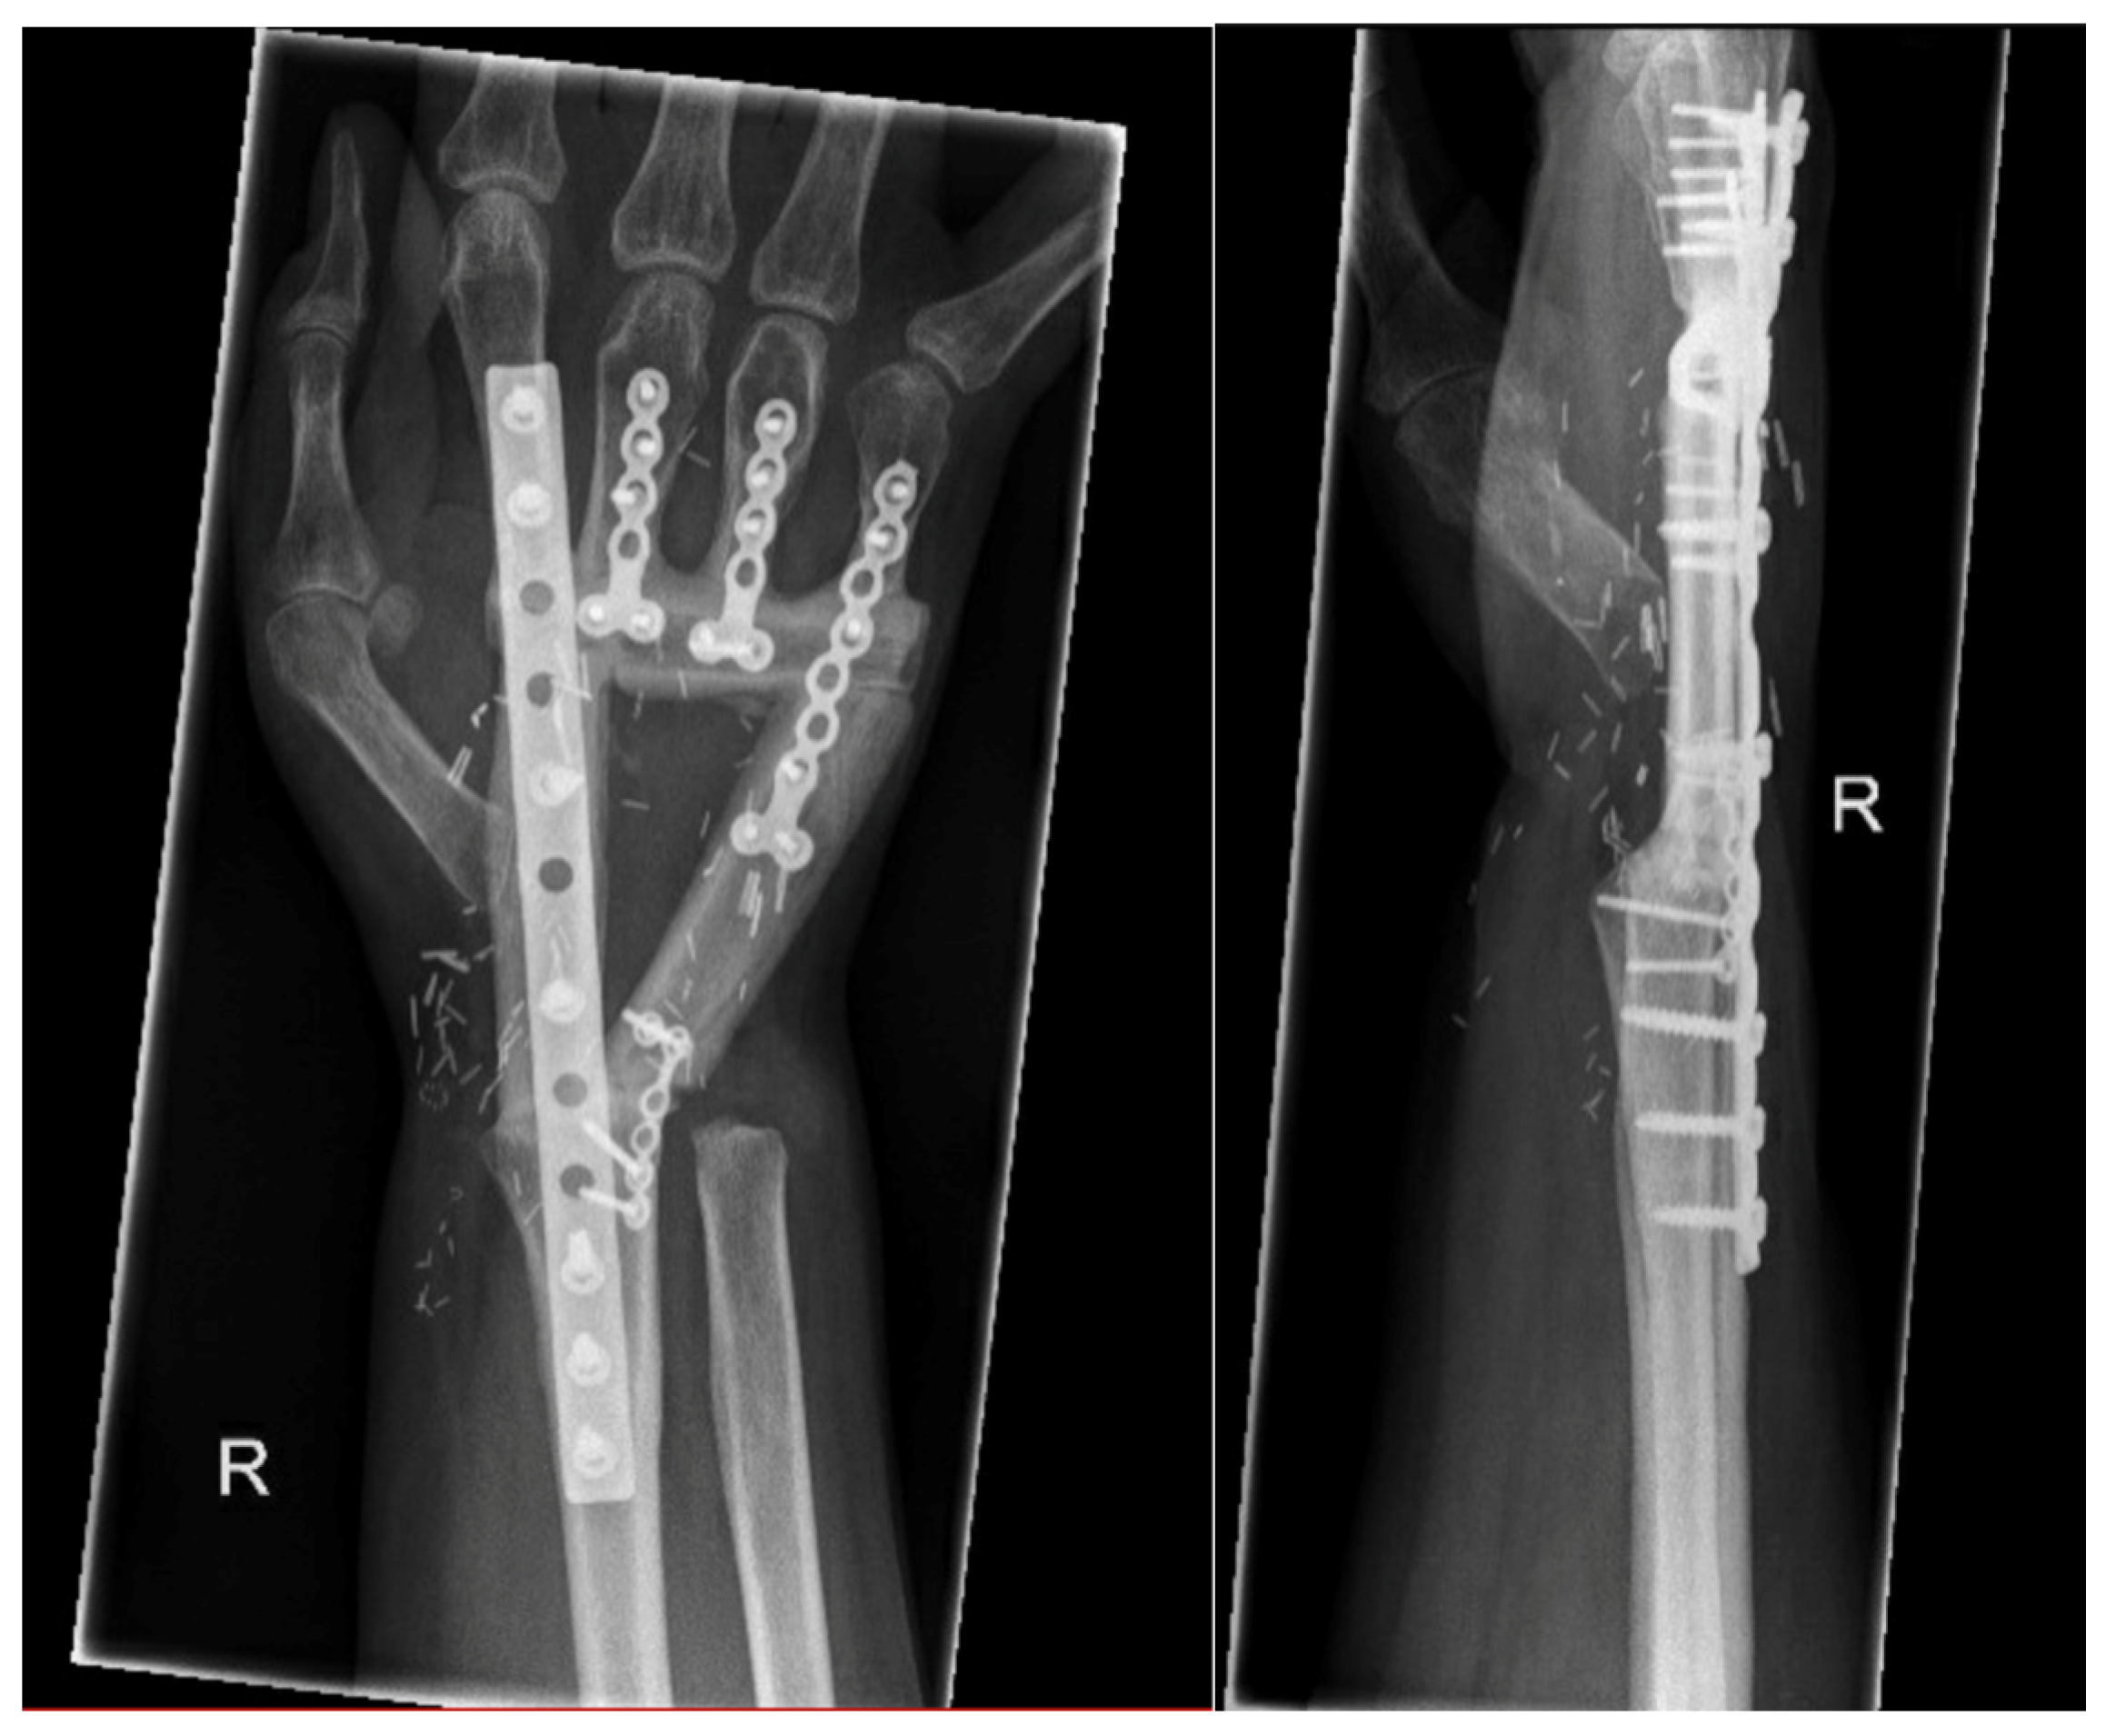

3.2.2. Arthrodesis of the Distal Radius and Middle Hand Using a Triangular-Shaped Vascularized Osteocutaneous Fibula Flap

| Case 3 | Complete wrist, distal radius and proximal metacarpals | Benign, aggressive bone tumor | 53 | 41 | 8 cm | Vascularized osteocutaneous triangular fibula | Wrist arthrodesis | N/A N/A | 0-0-0° 80-0-40° | 70% | MMWS = 45 DASH = 30 | yes | |